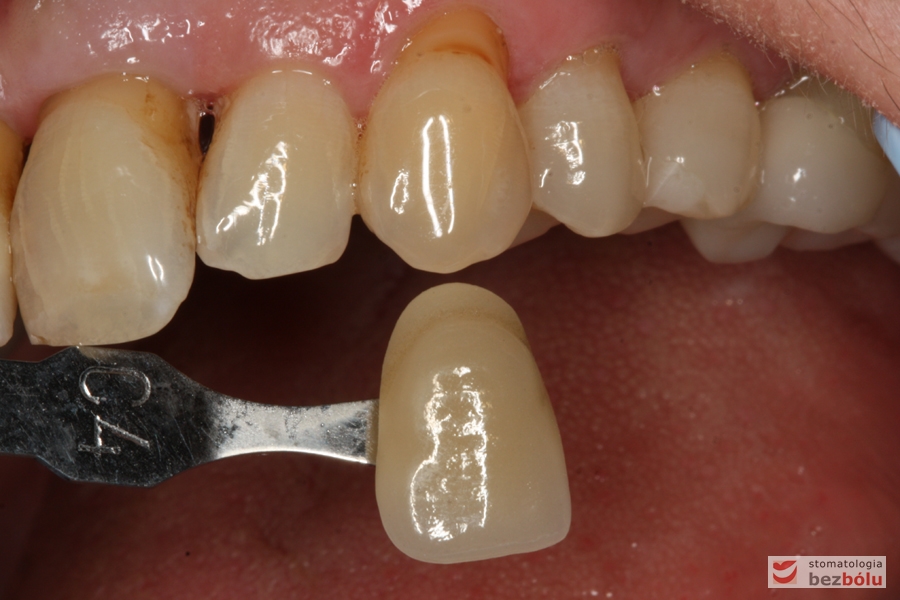

Dobór koloru ostatecznej odbudowy protetycznej - dopasowanie odcienia do barwy kła i antagonistów

Dobór koloru ostatecznej odbudowy protetycznej – dopasowanie odcienia do barwy kła i antagonistów